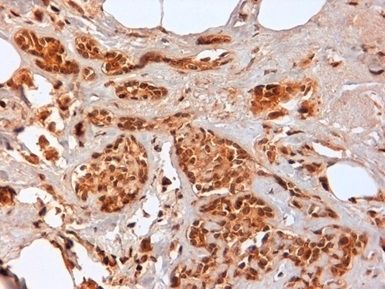

IHC-P analysis of human breast cancer biopsy tissue using GTX30725 CD44 antibody [F10-44-2].